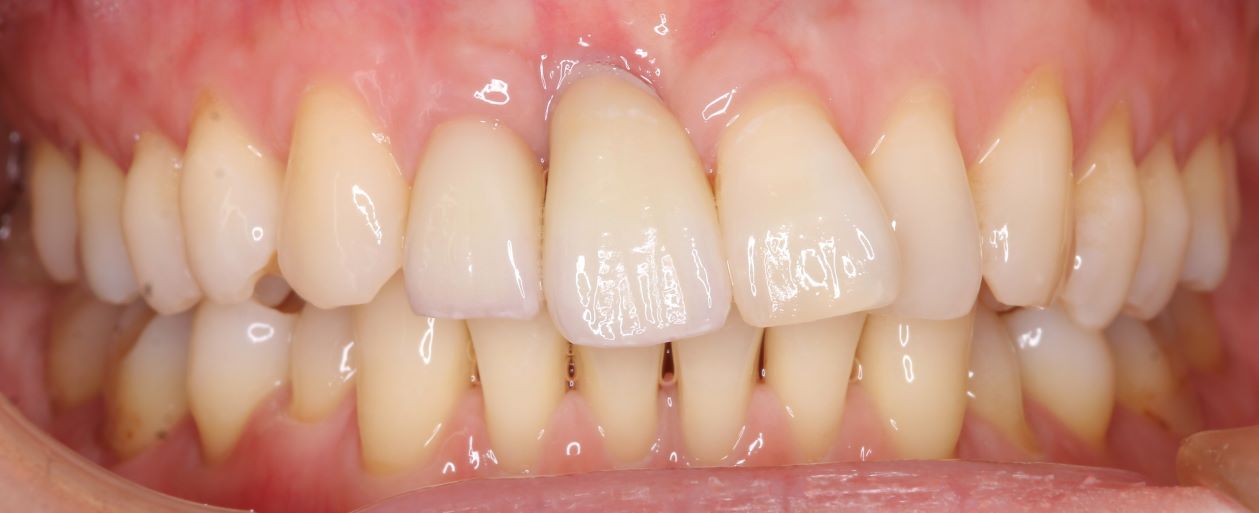

case 02.

BEFORE

AFTER

見た目を重視した治療を希望されている

(リスク)